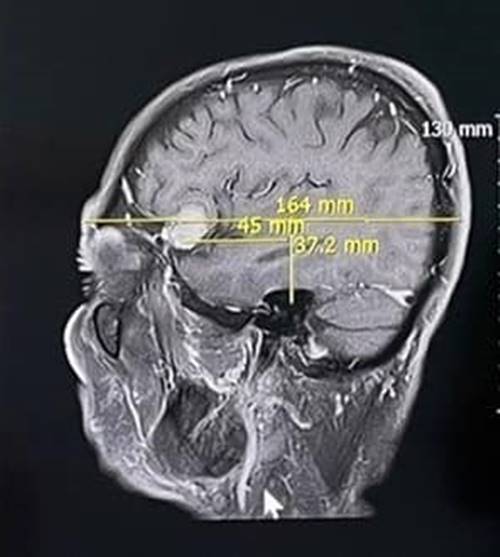

เบื้องต้น แพทย์ส่งไปตรวจแผนกหู คอ จมูก ตั้งข้อสงสัยอาจมีความผิดปกติทางสมอง จึงส่งตรวจคลื่นแม่เหล็กไฟฟ้าสมอง พบเนื้องอกในสมอง 2 เซนติเมตร จึงตัดสินใจผ่าตัด งานนี้ค่อนข้างยาก ต้องใช้ทักษะและประสบการณ์อย่างสูง เพราะนอกจากต้องแก้อาการปวดหัวให้หายเป็นปกติแล้ว ต้องไม่มีอาการแทรกซ้อนอื่น ๆ ตามมา ยิ่งก้อนเนื้อมีขนาดใหญ่ ยิ่งมีผลกระทบต่อร่างกายเท่านั้น